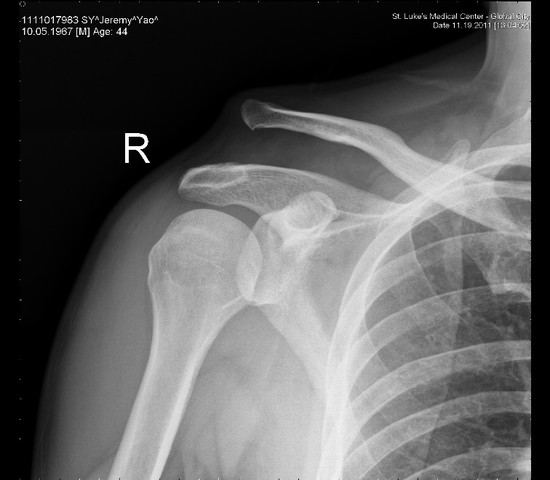

• shoulder diverging

shoulder diverging

The day I seperated my shoulder when I scrambled out of the pocket and through a pass to my wide reciever. I tried to get a nice play to him but I took to long, although I still have never made a mistake in my life. Perhaps I held it a little too long.